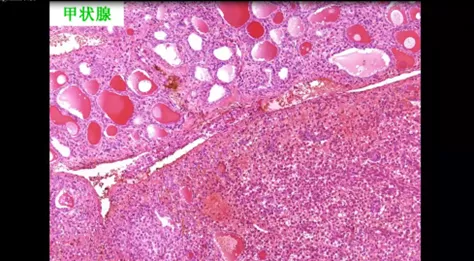

刘老师结合工作的具体实例,从理论到实践全面的阐述了免疫组化基本原理、注意事项、在诊断中的主要要点。

2-免疫组化对病理诊断的重要性.png 3-甲状腺.png

• 免疫组化对病理诊断的重要性 江西省人民医院 刘勇